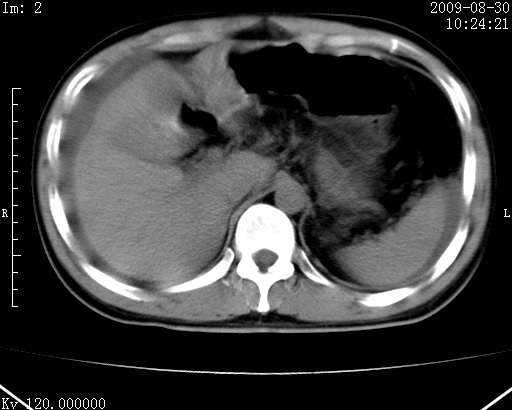

患者唐某,男31岁,已婚,本地务农。

自述入院前两天一次进食较多冷饮之后,出现阵发性上腹部疼痛,次日加剧伴恶心、呕吐,呕吐后症状稍减轻。食欲差。大便每天1-2次,量少,暗红色水样。小便赤。无畏寒、发热、咳嗽等呼吸道症状。无高血压及胃病史。

检查:体温、血压及脉搏正常.皮肤无黄染,浅表无淋巴结肿大。左腹肌紧张,左上腹有压痛,无反跳痛,可触及包块。

生化:钾、钠、氯、钙、ph正常,总胆红素和直接胆红素稍高,空腹血糖稍高。

尿淀粉酶:1256 u/l(正常60-401)。

血常规:wbc 22.4x109/l gr88% ly9.6%其余基本正常。

胃镜:急性胃炎。立位腹平片:未见异常。

下面是ct平扫,降结肠内是对比剂。

术前影像诊断:上段空肠急性缺血性坏死并腹水。建议手术治疗。

术中见上段空肠约70cm长范围坏死,从屈氏韧带远端约10cm处开始。坏死肠管肿胀变形变色,管壁明显环形增厚,部分聚成大肿块,无扭转和套叠。肠系膜上动脉分支内广泛泥沙状血栓。肠切除。

临床诊断:肠系膜上动脉梗塞并急性肠坏死。

开始时我们科也有人认为是套叠,最后统一意见,不考虑肠套。我们看到的“靶征”,“晕圈征”,“双圈征”实际上只是单根肠管的横断面。坏死肿胀后肠壁各层的密度不一样。

左侧腹小肠腔管壁明显增厚,部分内示靶征,走行异常,部分肠系膜绳样改变,肝包膜下及肠间较多液体密度,然梗阻近端肠腔积气不明显。

考虑;肠扭曲伴肠坏死。

腹部肠管肠管弥漫性增厚、肿胀,考虑为肠管缺血或淤血改变,未排除空肠管坏死。腹水。

有结果了,回顾分析,套叠只会在局部出现同心圆征,不会很长一段肠管都有,还是水肿坏死。